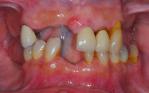

Replacement of all upper teeth with implant supported ceramic bridgework, and implant crowns to replace the missing lower teeth.

After